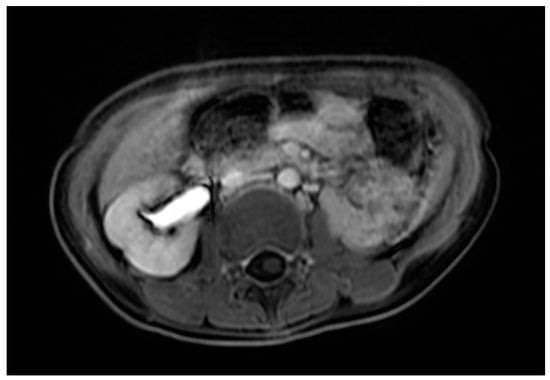

Case 3 was a female infant born at 34 weeks of gestation. The antenatal ultrasound showed fetal ureteral obstruction and oligohydramnios. She had a poorly developed vestibule with a small orifice near the clitoris and high-type imperforate anus, indicating cloacal malformation. A double-barrel colostomy and drainage of 30 mL turbid urine of the orifice of the common channel, possibly from the distended vagina, was performed at 5 hours of age. Abdominal ultrasound at 1 day of age showed a 7.5 cm cystic mass in the lower abdomen, but it decreased in size on the next day. Water instillation via urinary catheter visualized the urinary bladder and enlarged the cystic mass on real-time ultrasound, suggesting HMC with vesicovaginal fistula. The patient received spinal lipoma excision at 8 months of age for the lipomyelomeningocele, and repair for tetralogy of Fallot at 1 year of age. Posterior sagittal anorectovaginourethroplasty using the Pena method was performed at 1 year, 8 months of age, and the distal vagina was replaced by a 5 cm length of rectum. She began menstruating at 12 years, 10 months, which was associated with cyclic abdominal pain, and the MRI detected uterine didelphys with left hematometrocolpos, hemivagina, and left renal agenesis (Figure 4 and Figure 5). Hysteroscopy was performed via the neovagina, and one bulging mass in the left side was observed. The right uterus cavity was normal with smooth endometrium. Herlyn–Werner–Wunderlich syndrome was diagnosed. The patient anticipates left hemi-hysterectomy and transcervical resection of the vaginal septum.

Figure 5.

MRI of case 3: left renal agenesis and right hydroureter.